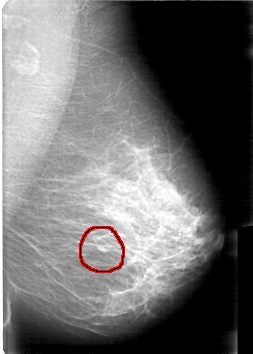

D_4065_1.RIGHT_MLO

FILE: D_4065_1.LEFT_MLO.OVERLAY

TOTAL_ABNORMALITIES 1

ABNORMALITY 1

LESION_TYPE MASS SHAPE OVAL MARGINS OBSCURED

ASSESSMENT 0

SUBTLETY 4

PATHOLOGY BENIGN

TOTAL_OUTLINES 1

BOUNDARY